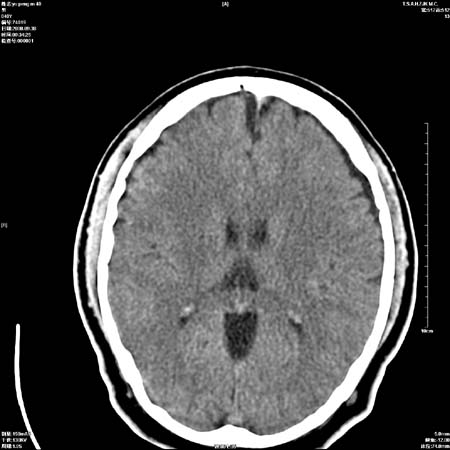

以下是引用zjzjr在2008-10-4 20:29:00的发言:[br]右颞叶皮质区密度略减低,脑沟较对侧变浅,考虑早期脑梗塞,建议mri.左侧小脑幕缘旁可见带状低密度影,轻度占位效应,支持蛛网膜囊肿,枕大池区亦考虑蛛网膜囊肿.

以下是引用流浪星在2008-10-4 20:06:00的发言:[br]大脑大静脉池增宽,脑萎缩引起,目前的ct表现不能解释临床症状,建议短期复查或做mr检查。